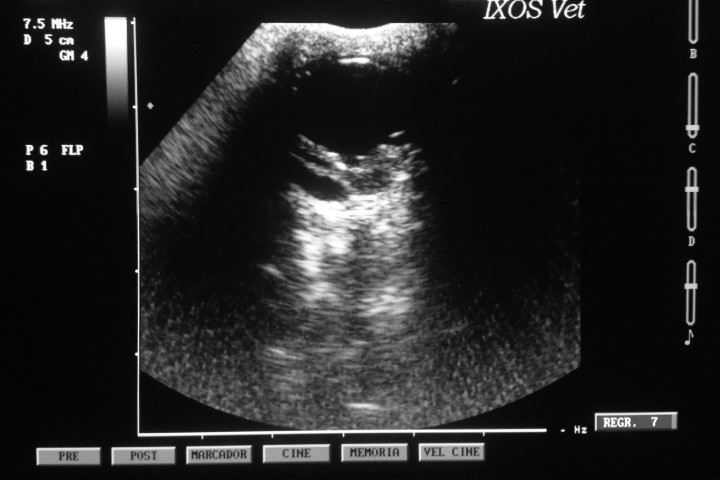

Se realizó oftalmoscopia directa (Welch-Allyn®, Nueva York) del OD previa dilatación pupilar con tropicamida (Colircusí Tropicamida®, Alcon Cusí, Barcelona), así como oftalmoscopia indirecta con lente de 20 dioptrías y un transiluminador de Finoff (Welch-Allyn®, Nueva York). Se tomaron fotografías del fondo del ojo (PanOptic® y accesorio iExaminerTM para iPhone®4S, Welch-Allyn®, Nueva York) que no revelaron anomalías del fondo ocular (Fig. 6). Al no poder observarse el segmento posterior del OS se realizó una ecografía ocular que mostró desprendimiento de retina y adherencias entre iris y cristalino sin presencia de catarata asociada (Fig. 7).

<p>Ecografía del OS; obsérvese el desprendimiento de retina en segmento posterior y la acusada disminución de la cámara anterior.</p>

Figura 7

Ecografía del OS; obsérvese el desprendimiento de retina en segmento posterior y la acusada disminución de la cámara anterior.